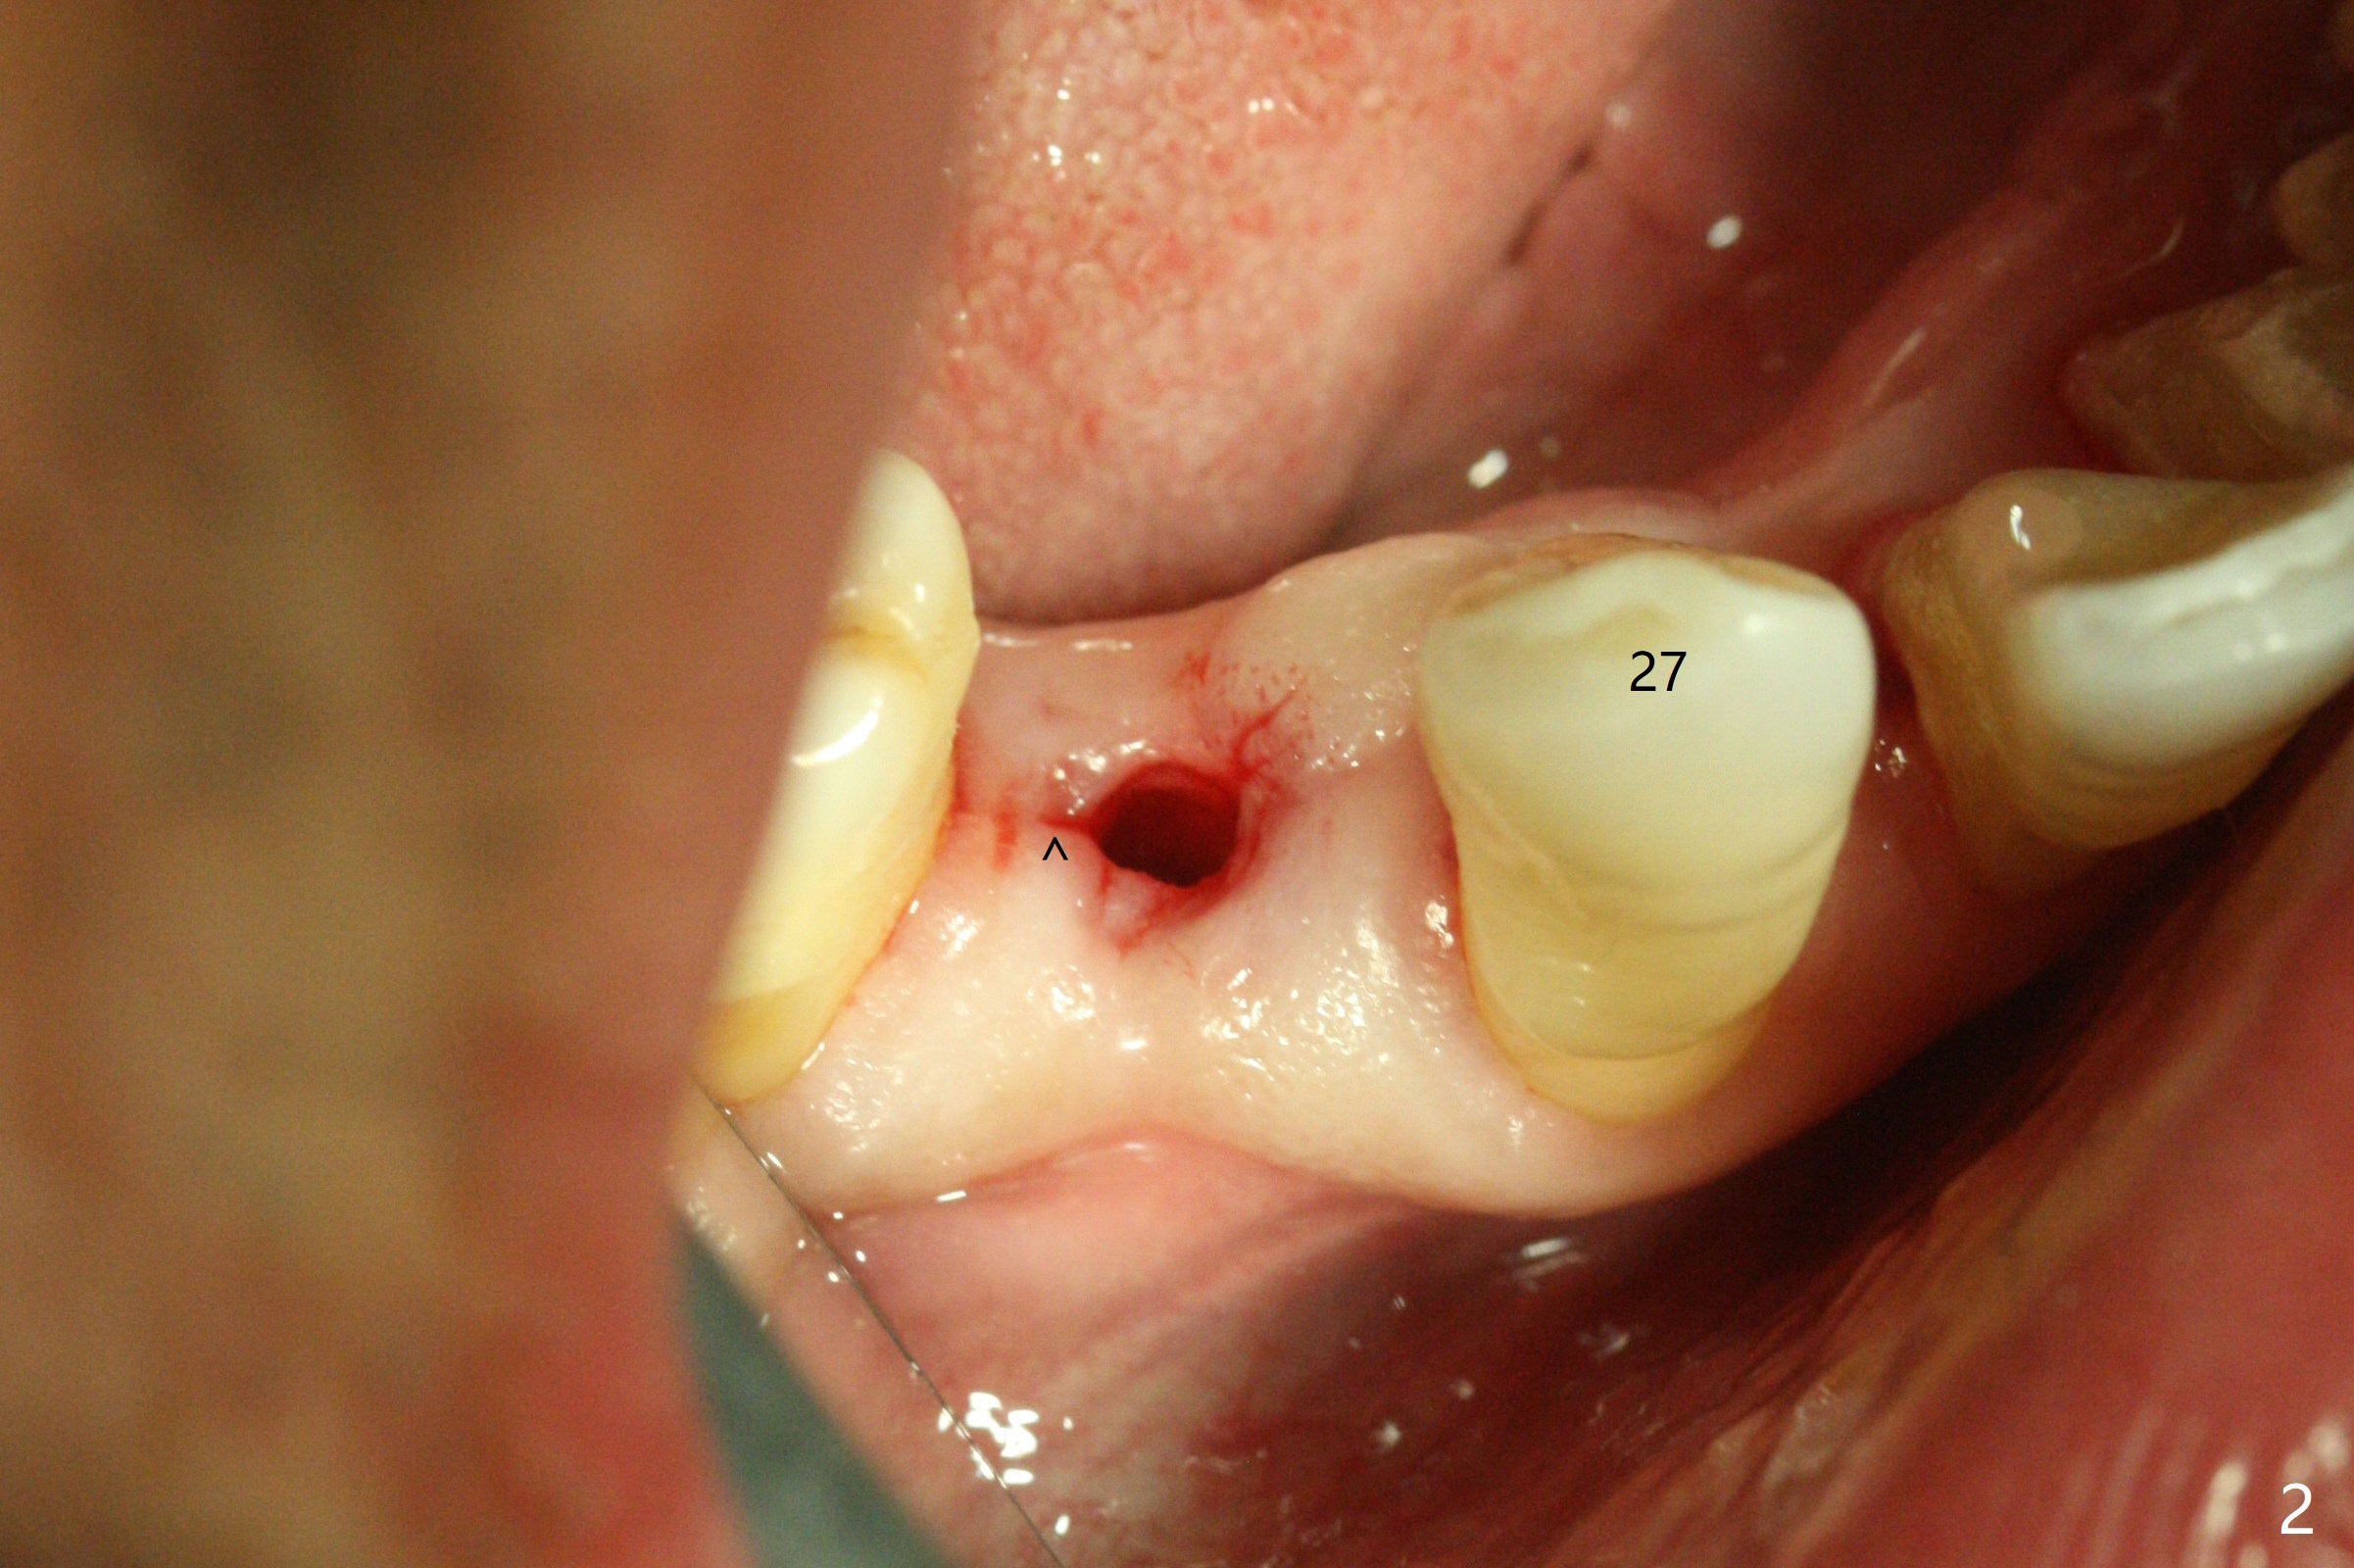

With 9 mm offset, the cylinder portion of the 2.2x8.5 mm drill does not engage to the metal sleeve of the guide at #28 after pointed drill (Fig.1). This issue could be solved with 12 mm offset, although it has no ill effect in this case. Fig.2 shows the site of #28 immediately before bone expansion and after use of 2.2x11.5 mm drill and small-scaled ridge split (^). The bone is so hard that the bone expansion is minimal (Fig.5) with autogenous bone graft and implant placement (Fig.4). There is the bone buccal to the implant clinically. A 5x10 mm implant is placed at #31 in the same appointment (Fig.3). Because of inability to masticate on the left (#18 root fracture with infection), the patient wants to restore #28 and 31 implants 3 months postop (Fig.6,7). The implant at #28 is removed while the healing abutment is being un-torqued without noting bone loss mesially (Fig.7 * (next similar case)). Bone graft is placed (Fig.8 (*),9). Pay attention radiolucency next the apex of the neighboring tooth (Fig.9 ?) before re-placement of an implant. The patient is upset, since he cannot eat. Two weeks later, a 6.5x4(4) mm cemented abutment is placed with 25 Ncm at #31 with a provisional for progressive loading for 2 weeks. Impression is taken. Two weeks later, a permanent crown is cemented without removing the underlying abutment. Two days later, the crown/abutment dislodges; a 6.8x6 mm healing abutment is placed. Eight days, it is difficult to reseat the existing crown and abutment. The mesiodistal edentulous space is limited as well. A 5.2x4(4) mm cemented abutment is able to be seated and torqued (30 Ncm) smoothly; in fact the clearance from the crestal bone (Fig.10 *) is not ample. If the abutment screw becomes loose in function, a profile drill should be used or a 4.5 mm in diameter abutment be placed. The abutment seems to remain in place immediate post cementation (Fig.11). Implant failure is probably due to no socket preservation (buccal plate atrophy) and too early restoration.